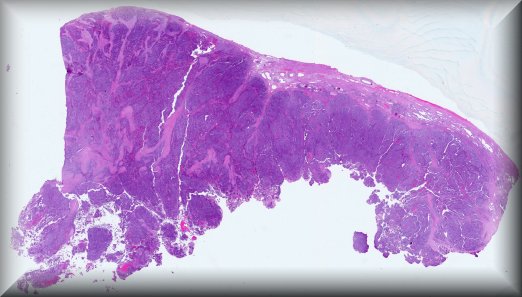

Varón de 86 años con masa testicular. Hombre de 86 años con antecedentes de diabetes mellitus tipo 2, hipertensión arterial, artrosis, fractura vertebral en T12 y apendicectomía, que acude a consultas de urología tras ser valorado en urgencias médicas ante sospecha de neoformación testicular. En la exploración física, se palpa masa pétrea ocupando polo inferior del testículo izquierdo, por lo que se solicita estudio ecográfico en el que se evidencia una lesión heterogénea con escasa señal vascular, que no parece depender de parénquima testicular y que les sugiere, sin ser concluyente, infiltración por linfoma. Ante los hallazgos descritos se decide orquiectomía radical izquierda vía inguinal para estudio histológico.